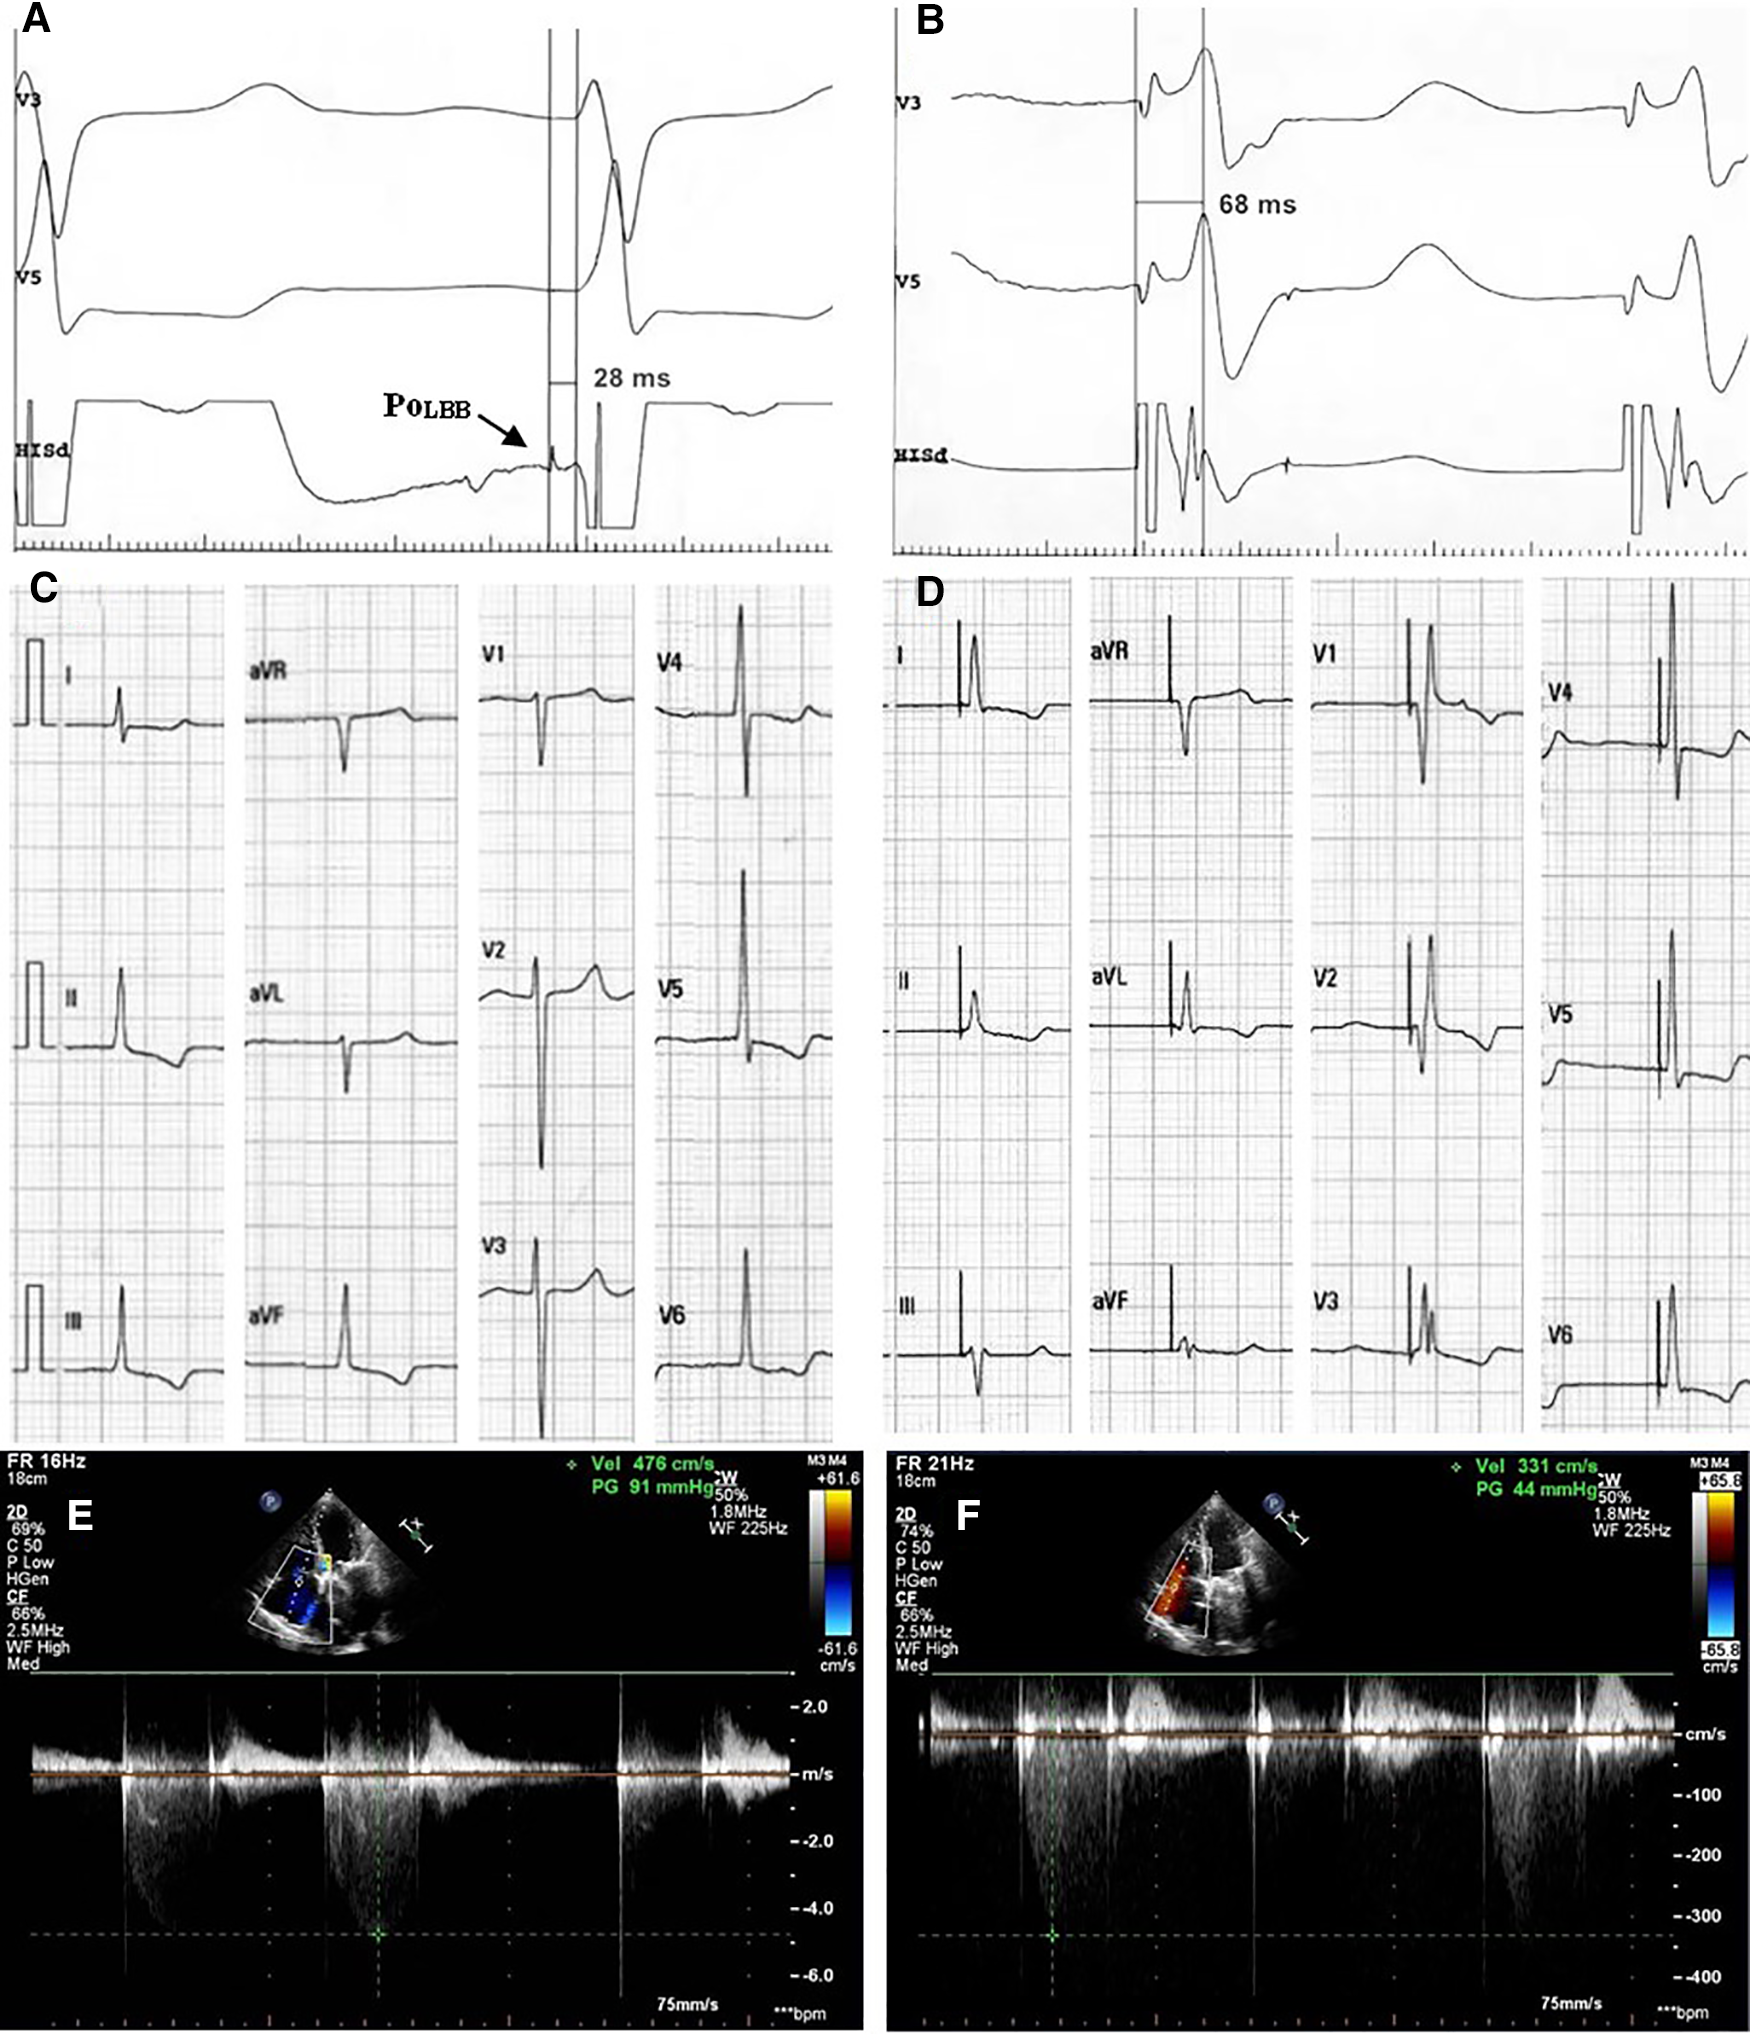

Case 6 was a 65-year-old male, who was admitted to the hospital because of rheumatic valvular heart disease and heart failure. His chief complaint was shortness of breath after exercise and edema of lower extremity for more than 30 years, which was aggravating for one month. The patient underwent mechanical mitral valve replacement 6 years ago. After adequate diuretic treatment, the patient's symptoms were not completely resolved. The echocardiography showed that the mechanical mitral valve worked well and LVEF was 69%. But he had severe tricuspid regurgitation and his regurgitation velocity was 476 cm/s (Figure 3E). The electrocardiogram showed atrial fibrillation and heart rate was 40–50 bpm. The patient had definite bradycardia and was advised to implant a permanent pacemaker. During the implantation, the left bundle branch potential was captured (Figure 3A) and LBBP was successfully performed. The sti-LVAT was 68 ms (Figure 3B) and paced QRS duration was 104 ms (Figure 3D). After 3 months of follow-up, the patient's symptoms of heart failure were significantly improved. Echocardiography showed that tricuspid valve regurgitation reduced to moderate and the regurgitation velocity decreased to 331 cm/s (Figure 3F). The pacemaker programming found that the capture threshold was lower than that at implantation and the pacing ratio was 94%.

Figure 3

Clinical data of typical case. (A) Left bundle branch potential; (B) LBBP: sti-LVAT was 68 ms; (C) ECG before implantation; (D) ECG after implantation; (E) Echocardiography before implantation: tricuspid regurgitation velocity 476 cm/s; (F) Echocardiography at 3-month follow-up: tricuspid regurgitation velocity 331 cm/s. PoLBB, potential of left bundle branch; LBBP, left bundle branch pacing; sti-LVAT, stimulus to left ventricular activation time; ECG, electrocardiogram.